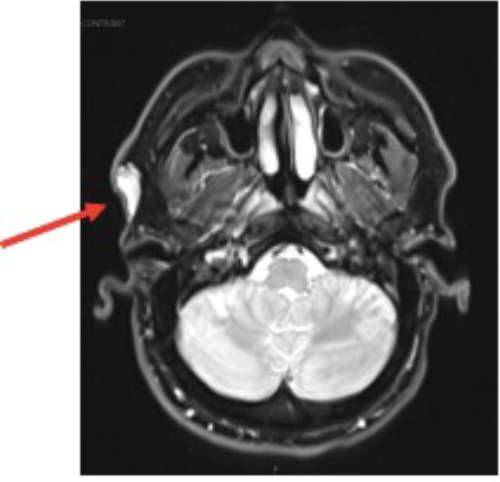

On physical examination, a 3 cm, non-tender, mobile, soft subcutaneous mass was palpated in the right preauricular region. Initial ultrasonography characterized the lesion as a hyperechoic soft tissue mass. Subsequent magnetic resonance imaging (MRI) revealed a well-circumscribed, non-specific lesion confined to the superficial soft tissues of the right preauricular area, without evidence of involvement of the underlying parotid gland or external auditory canal (Figure 1).

Figure 1. MRI of Preauricular Lipoblastoma. Published with Permission

Axial T2-weighted image showing the lesion (arrow) as predominantly hyperintense with some internal heterogeneity